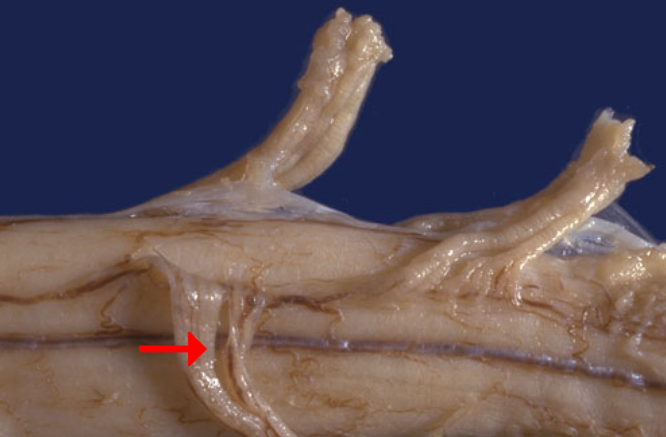

Label this region of the spinal cord

Dorsal sensory root

Label this region of the spinal cord

Ventral motor root